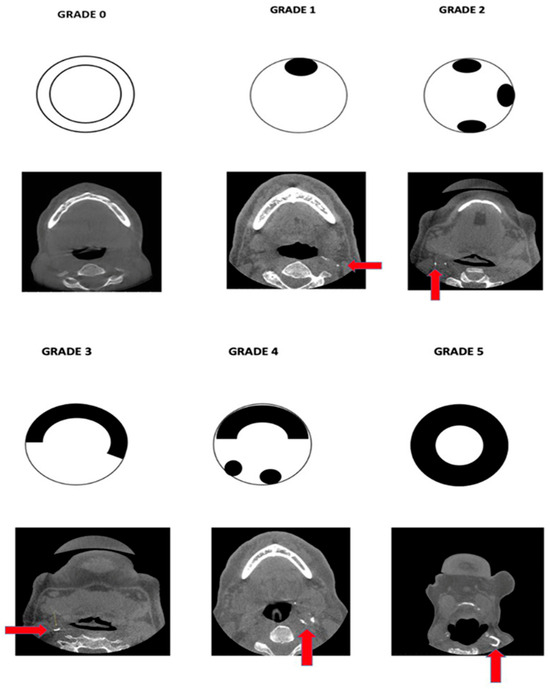

| Grade | Description |

|---|---|

| Grade 0 | No calcified plaque was present. |

| Grade 1 | Presence of a single speck of calcified plaque. |

| Grade 2 | Presence of more than one/multiple discontinuous specks of calcifications. |

| Grade 3 | One continuous semi-lunar band of calcification, covering at least half of the arterial lumen. |

| Grade 4 | One continuous semi-lunar band of calcification, covering at least half of the arterial lumen, along with one or more discontinuous calcified specks (Grade 2 + Grade 3). |

| Grade 5 | Circumferential coverage of the arterial lumen with calcified plaque. |